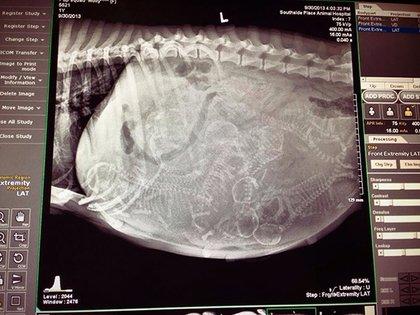

哈~這其實是動物懷孕的照片啦!美國《boredpanda》網站最近整理了一系列懷孕動物的X光照,從最常被人類飼養的貓、狗,乃至於蝙蝠、浣熊等都有,雖然小動物的誕生應該是可愛而溫馨,不過單看這些滿肚骨骸的X光照,還是覺得有點驚悚和詭異啊!

狗